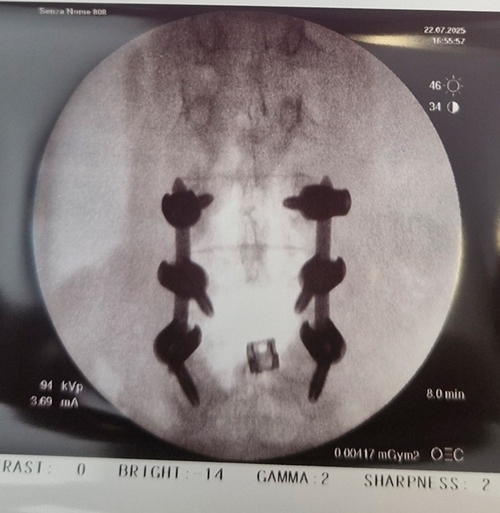

DIAGNOSI:

STENO-INSTABILITA’ LOMBARE MEDIANA

Risonanza magnetica lombare pre-operatoria

Intervento chirurgico eseguito:

PROCEDURA PLIF: POSTERIOR LUMBAR INTERBODY FUSION

Stabilizzazione vertebrale percutanea L4-L5 + introduzione di cage intersomatica PLIF Radiografia lombare post-operatoria